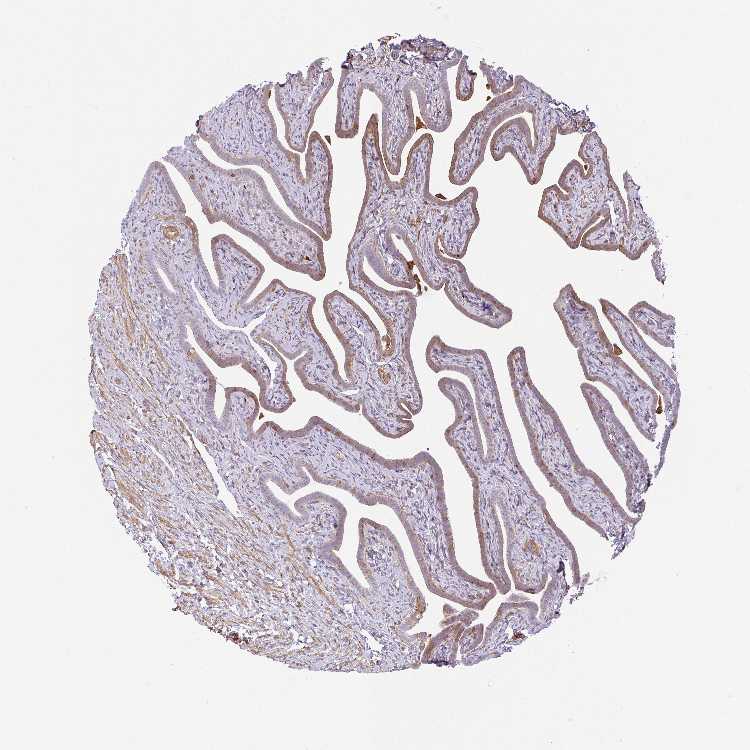

TISSUE PRIMARY DATA FALLOPIAN TUBE Show tissue menu

FALLOPIAN TUBE - Antibody stainingi

Antibody staining in the annotated cell types in the current human tissue is reported as not detected, low, medium, or high, based on conventional immunohistochemistry profiling in selected tissues. This score is based on the combination of the staining intensity and fraction of stained cells.

Each image is clickable and will lead to virtual microscopy that enables deeper exploration of all samples and also displays staining intensity scores, fraction scores and subcellular localization as well as patient and tissue information for each sample.

Antibody HPA054728

Ciliated cells (cell body) Low

Ciliated cells (cilia axoneme) Not detected

Ciliated cells (ciliary rootlets) Medium

Ciliated cells (tip of cilia) Not detected

Non-ciliated cells Low